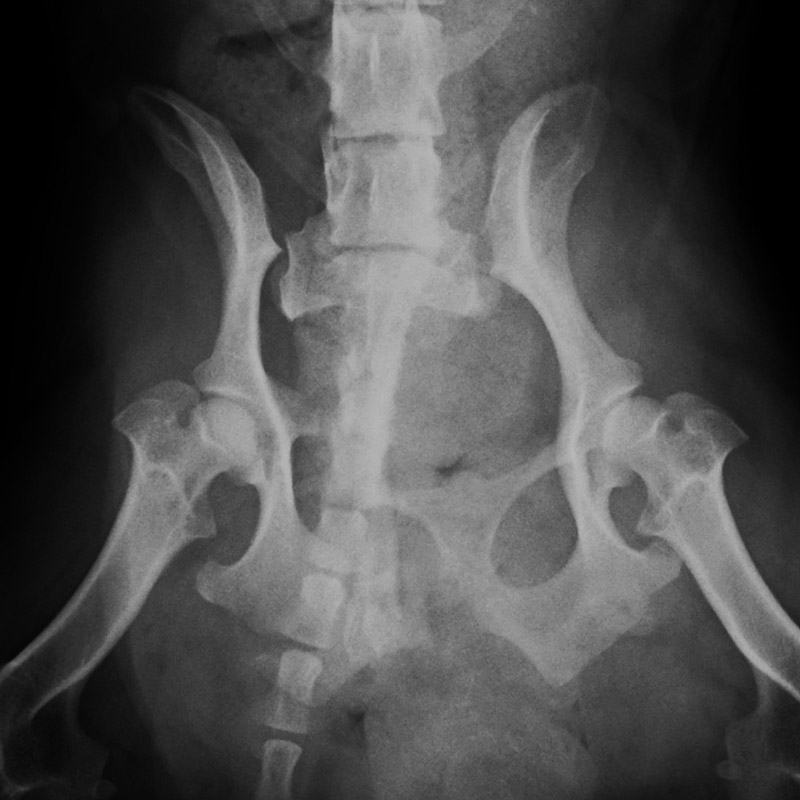

骨盤骨折

猫(2歳)

交通事故

手術前